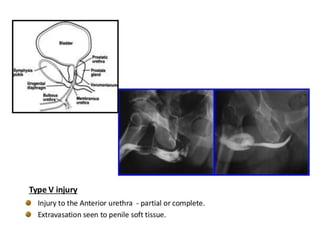

This document discusses the considerations and precautions for retrograde urethrography (RGU), noting that local anesthetic may cause issues such as mucosal edema. It highlights the need for antibiotic coverage due to potential complications like extravasation during contrast injection, and touches upon the role of cystography in pelvic fractures, indicating it can often be safely omitted. Additionally, it reports on complications related to urinary tract infections and reactions to contrast media, offering recommendations for patient management.